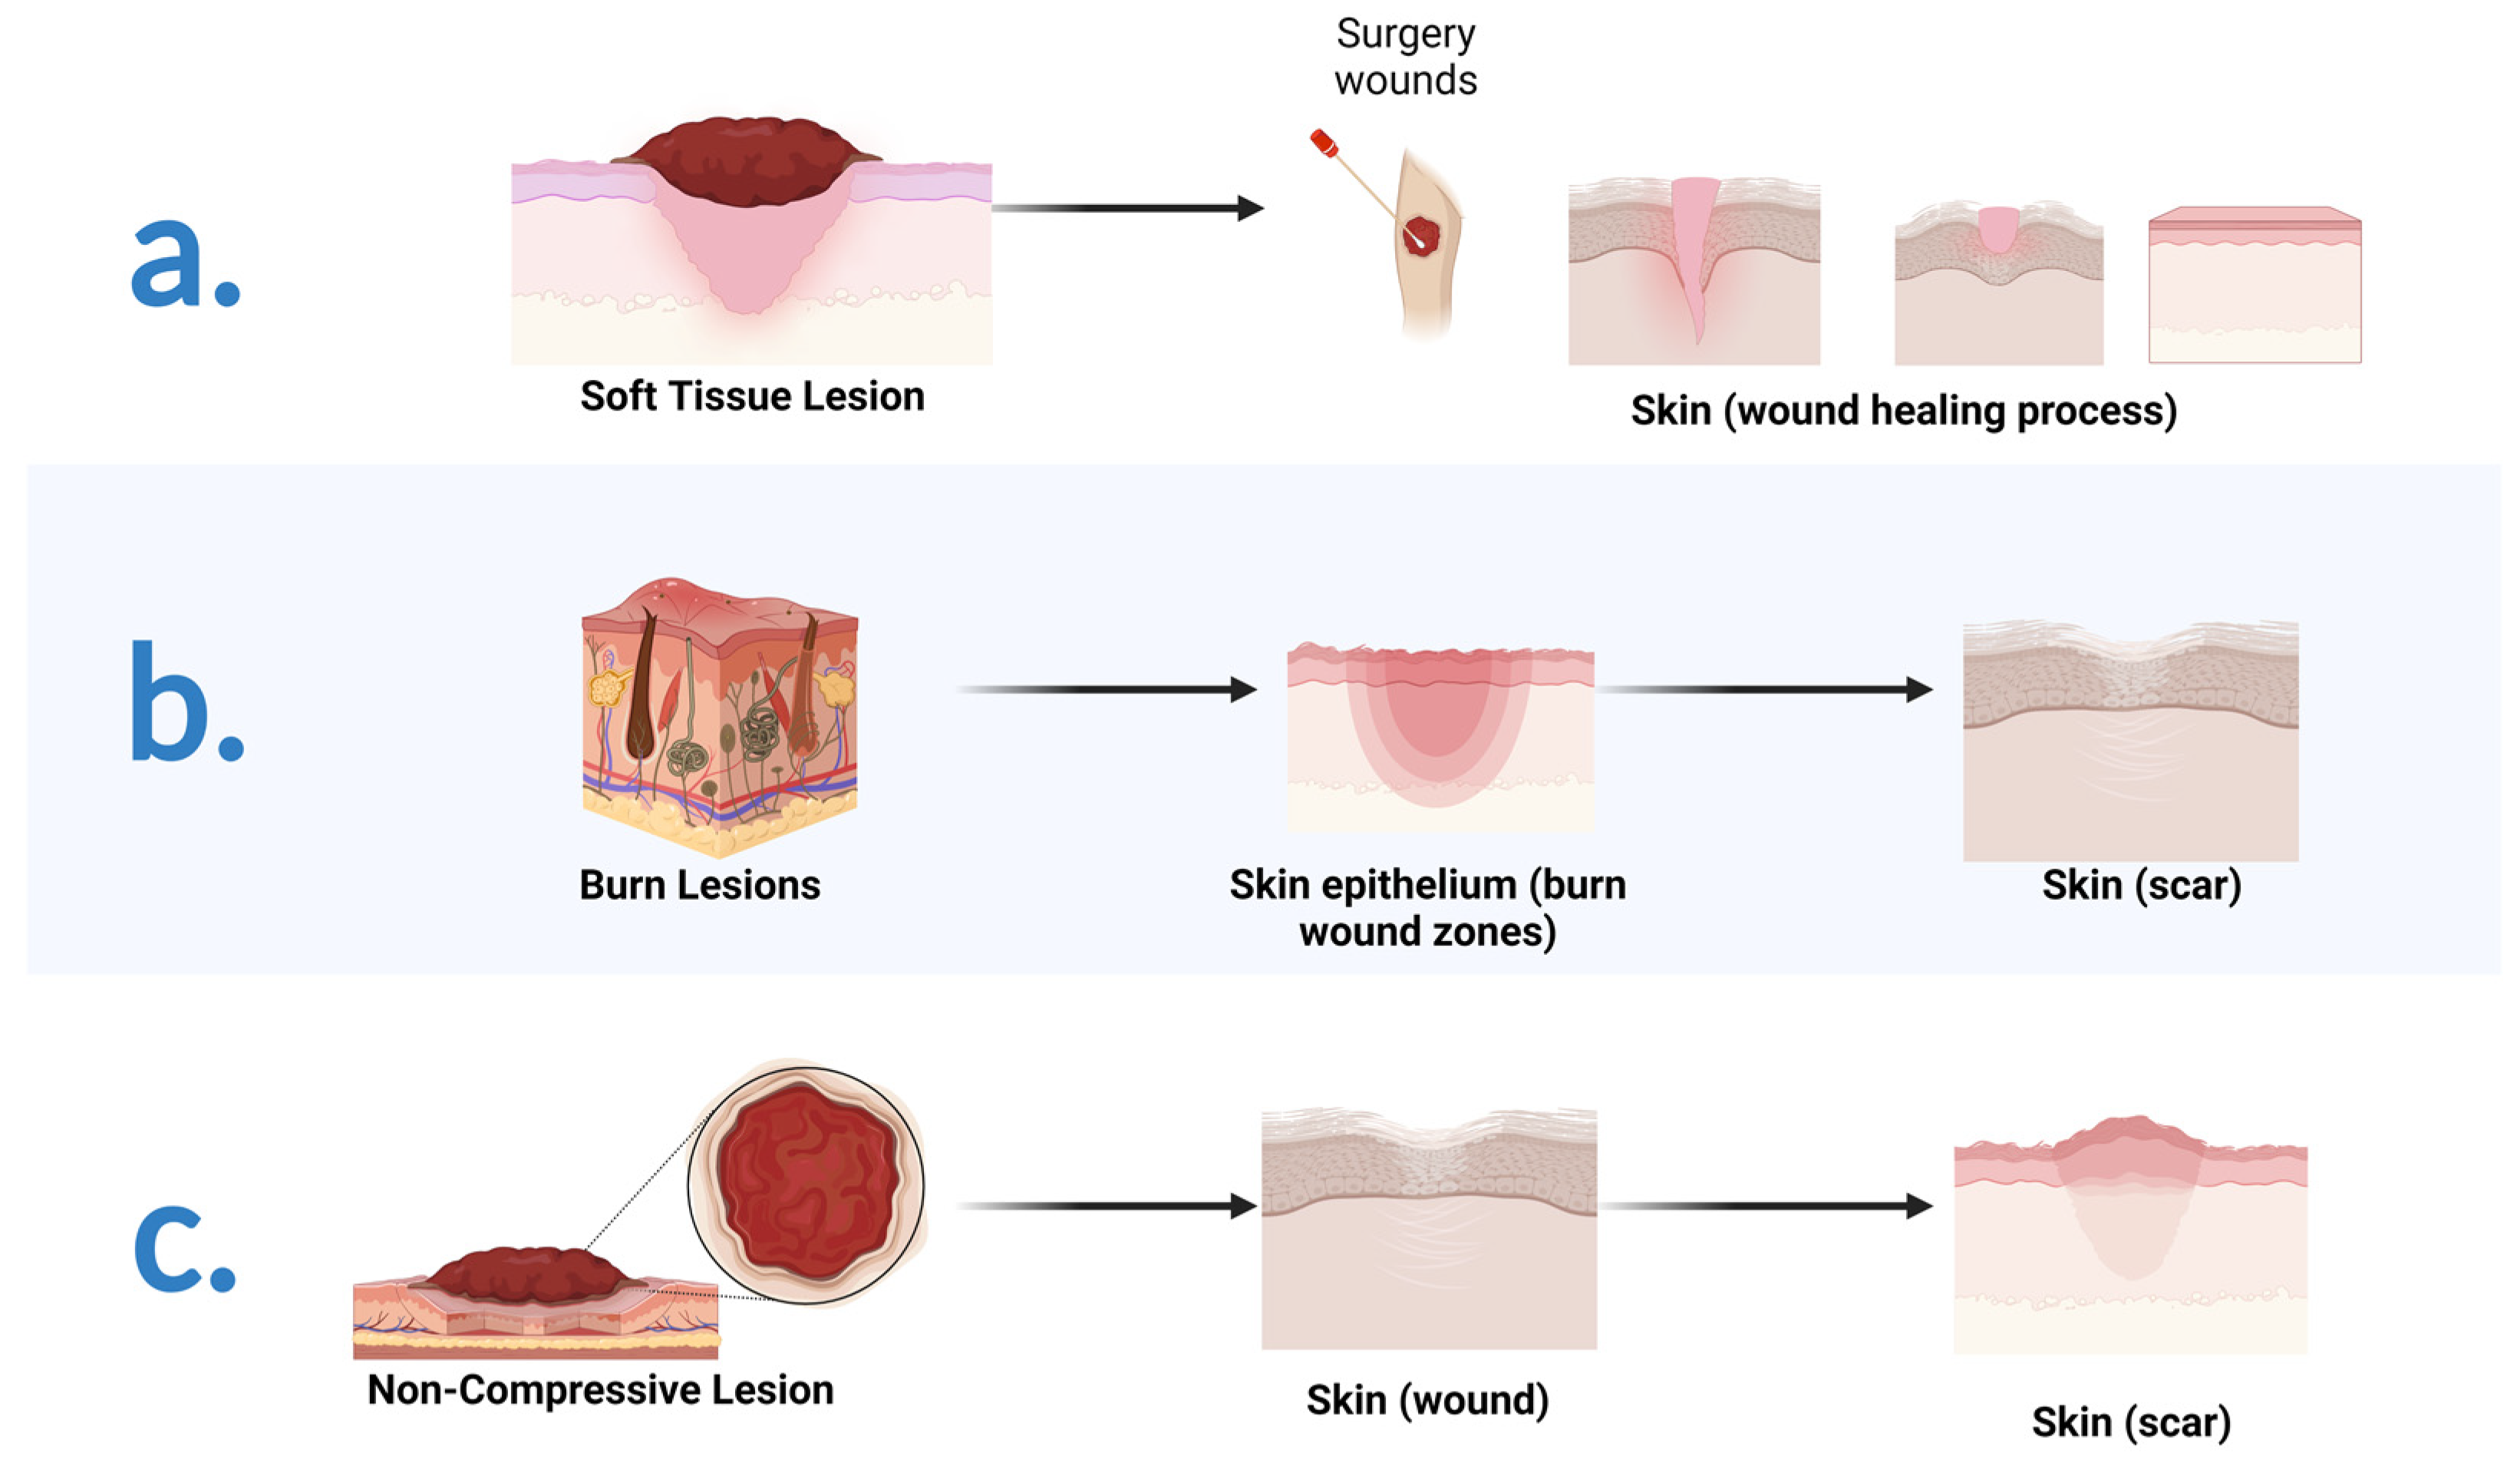

3. Soft Tissues Engineering

3.1. Wound Healing Mechanisms

3.2. Therapeutic Approaches in Wound Repair: A Brief Introduction